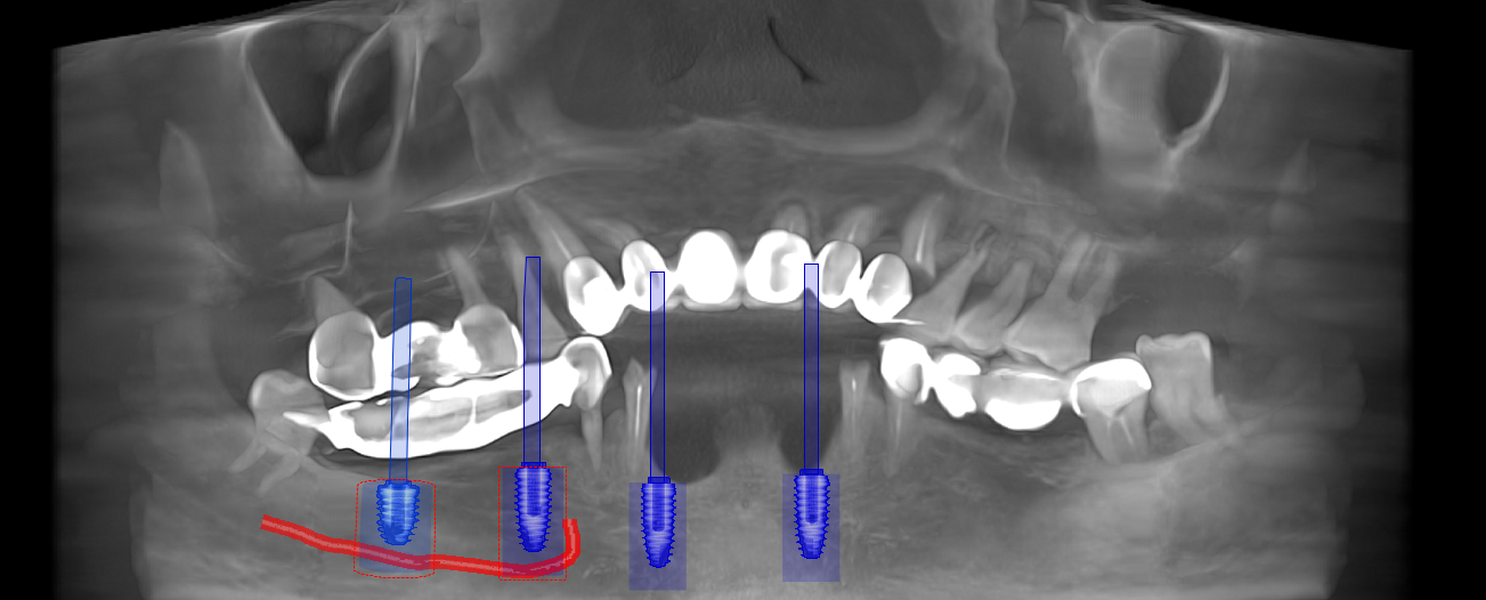

Tomografie (CBCT)

Caz 2